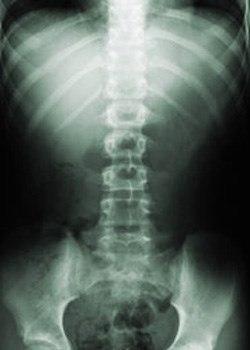

Researchers are one step closer to understanding how an individual's genetic make-up predisposes them to Ankylosing Spondylitis (AS), a common auto-immune arthritis which causes pain and stiffness of the spine, and in serious cases, progressive fusion of the vertebrae and other affected joints. The study is published recently in Nature Genetics.

"AS is notoriously difficult to diagnose in its early stages which can lead to costly delays in its treatment," said Dr Evans. "Typically diagnosis consists of a combination of X-rays, patient symptoms and expensive immunological assays in the laboratory. This genetic marker could easily take the place of an expensive immunological assay. What would normally cost £40-£50 could be done easily for a fraction of the price."